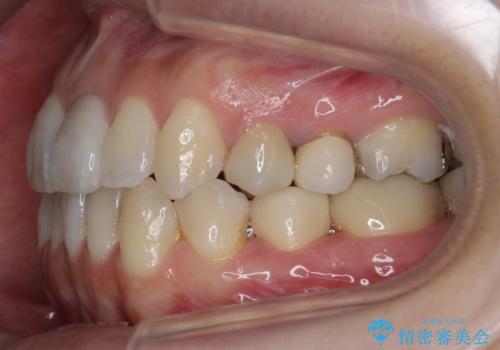

4本抜歯すると口元が下がりすぎてしまうため、下の前歯のみ1本抜歯および上顎の前歯が大きいため少し削らせてもらう提案をしました。

右上2番をしっかり並べるにはワイヤー矯正を上顎部分的に用いて、最後全体マウスピース治療を行いました。

上顎前歯は神経がない歯で色も変わってきていたためセラミックでかぶせています。